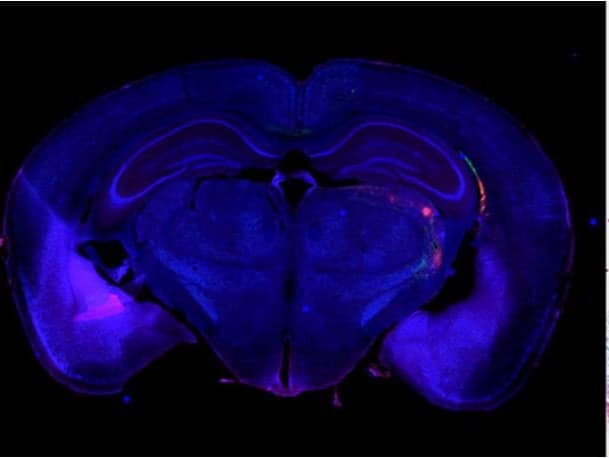

最終,高解析影像可幫助您建立大型標本的無縫拼接影像,例如小鼠大腦或組織切片。

首先預覽組織全貌,然後放大以觀察細節。